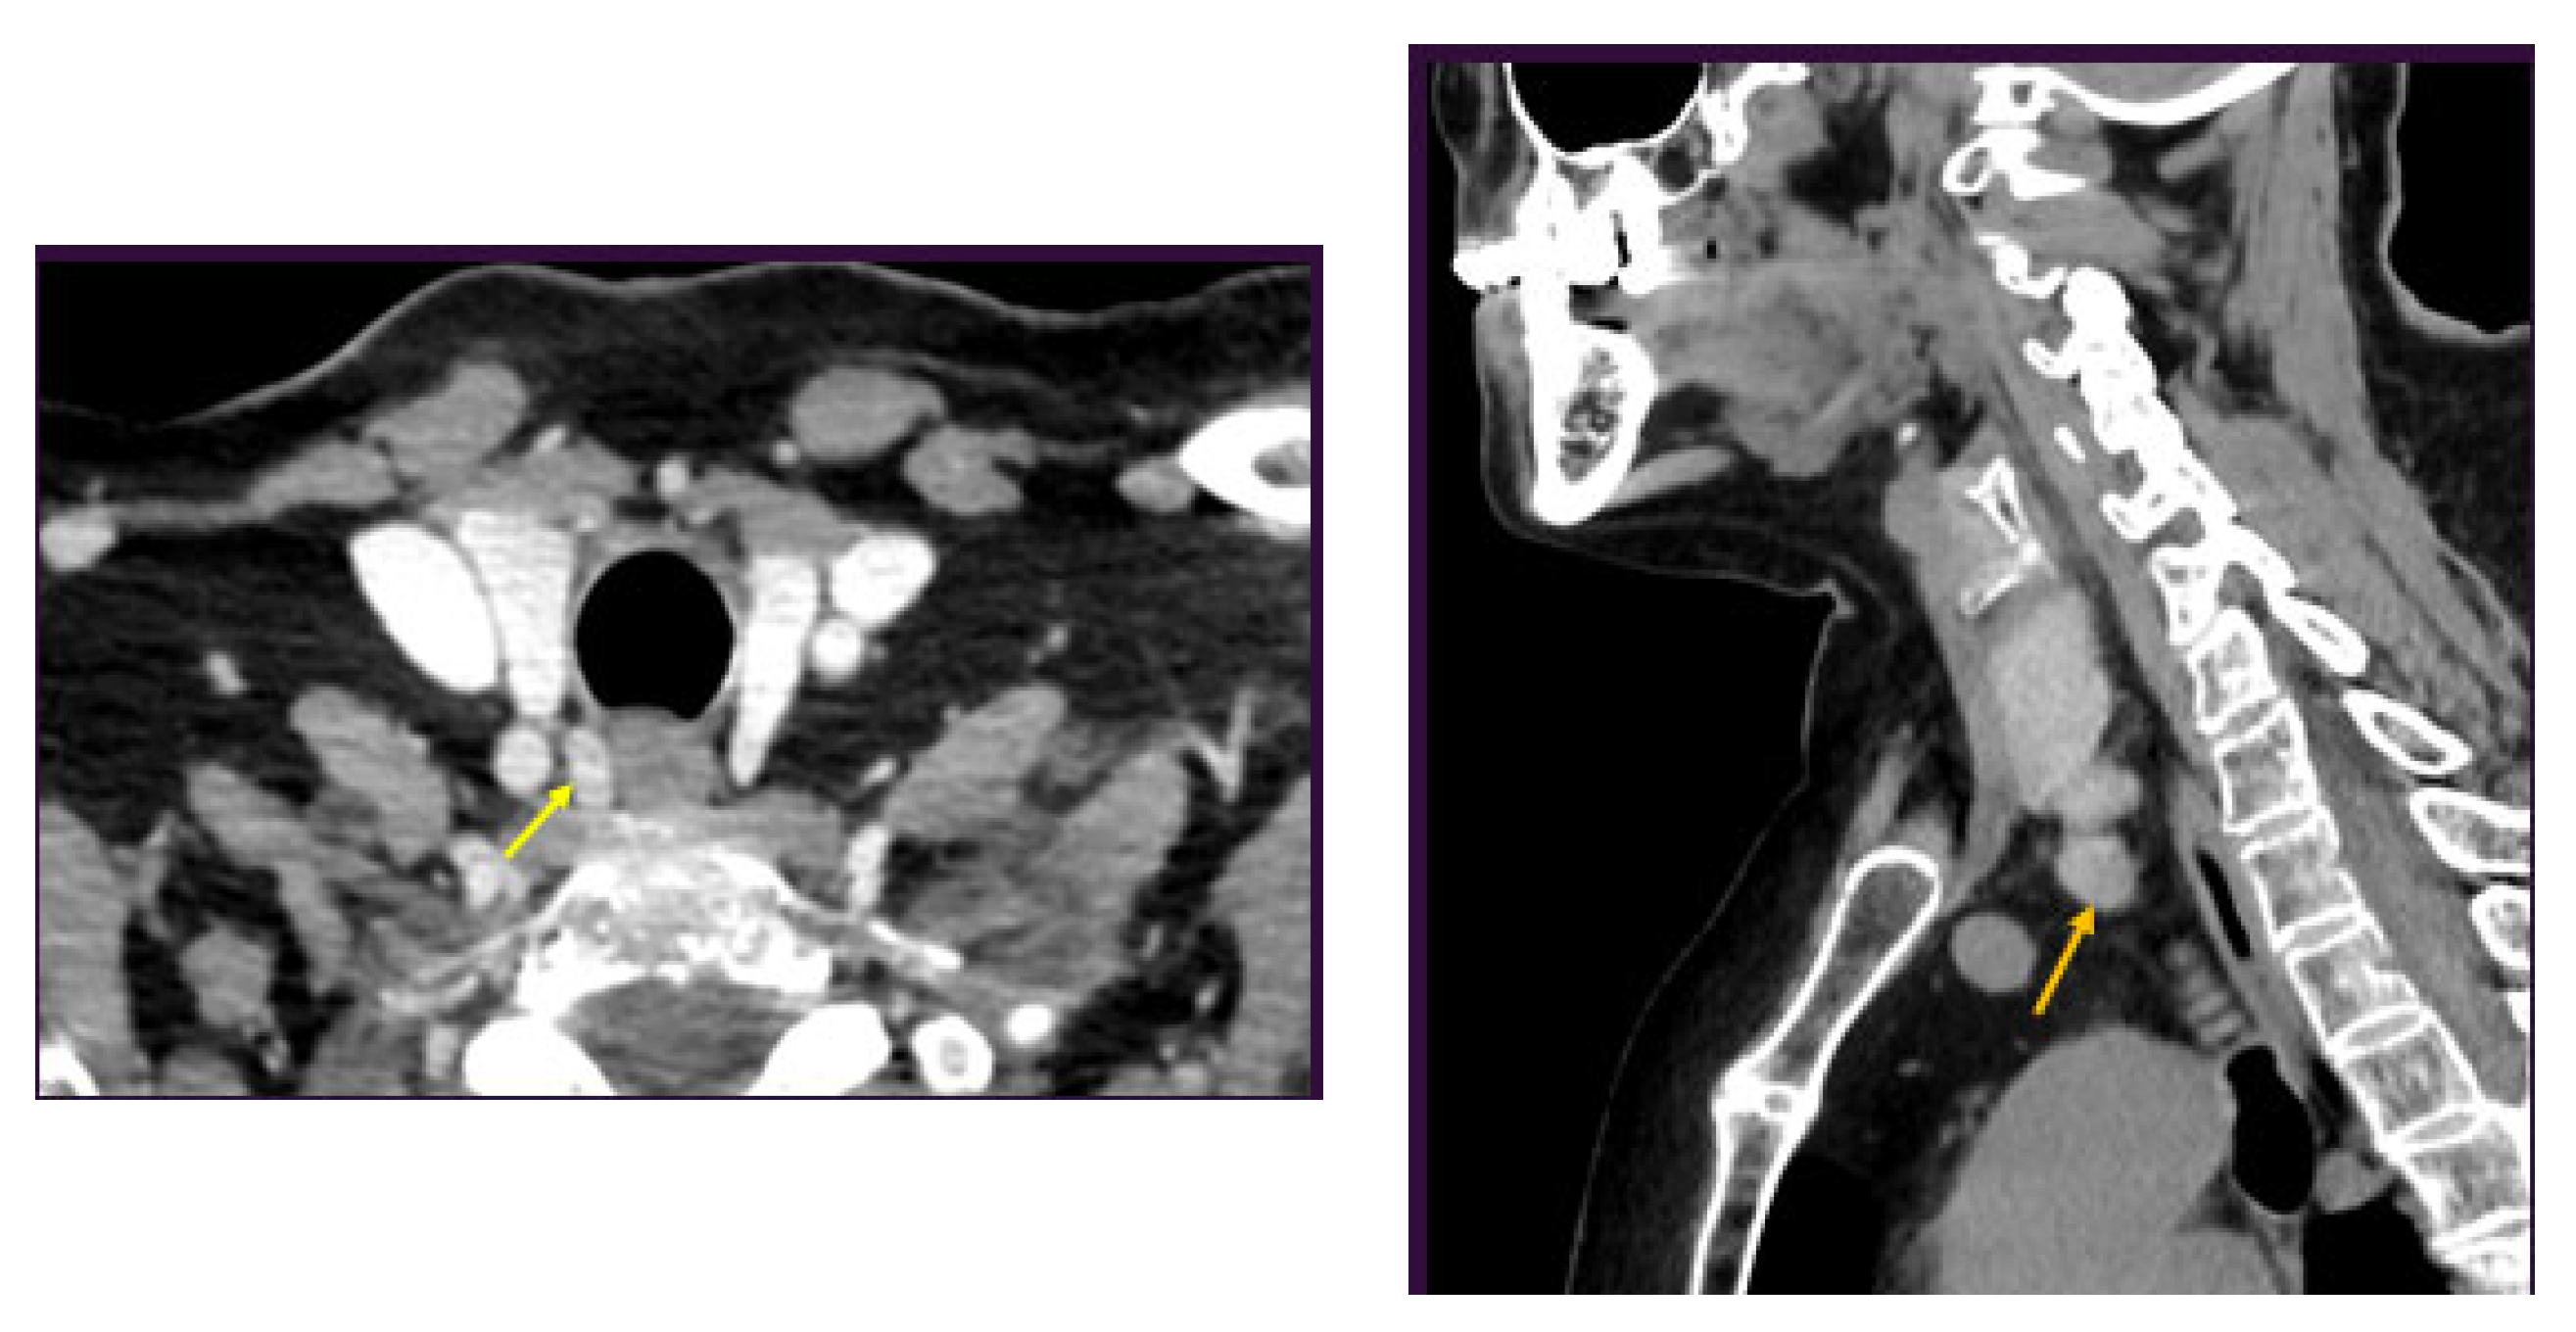

3. Clinical Vignette